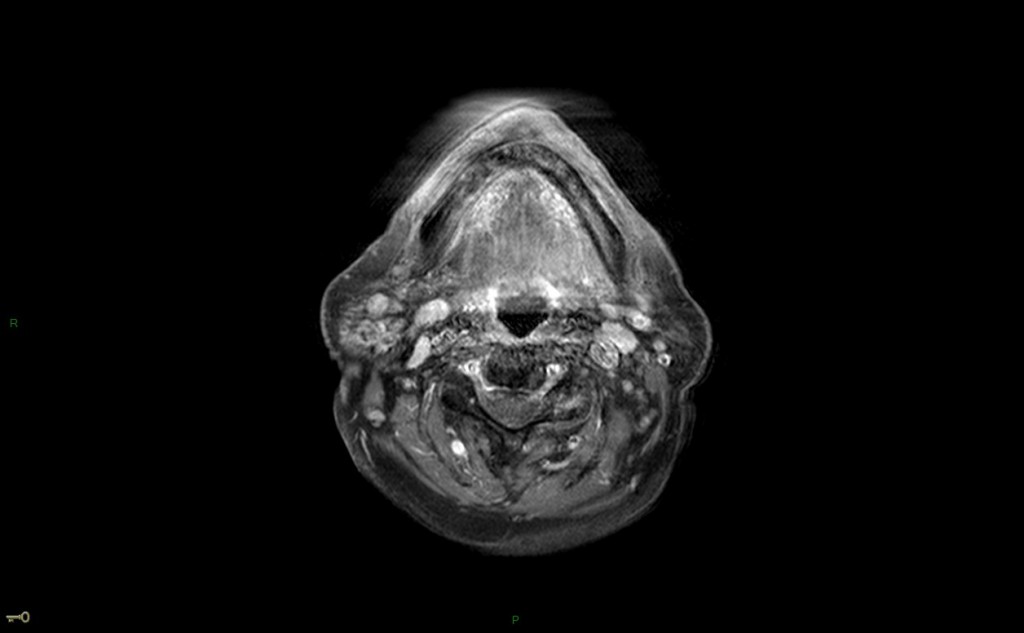

IRM : protocole d’exploration des tumeurs des glandes salivaires

• Axiale T1 et T2 SANS FAT SAT (avec FAT SAT si post opératoire)

• Axiale T2 ganglions cervicaux si tumeur maligne

• Axiale diffusion b0 b1000

• Dynamique axiale après injection de gadolinium, 40 phases, 2-3 s entre chaque phase

• Axiale et coronale T1 gado FAT SAT

• Reconstructions perfusion : ROI sur la lésion uniquement en zone tissulaire (en hT2), en dehors hémorragie ou kyste

• Reconstructions diffusion: ROI sur la portion tissulaire en dehors hémorragie, calculer un rapport avec parotide controlatérale

• Localisation : veine rétro-mandibulaire : en dehors: superficiel, en dedans : profond